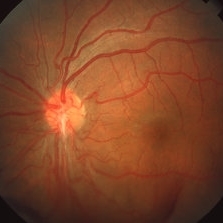

Posterior pole of the right eye of a 23-year-old Vietnamese female with Eales disease; V.A.= 20/40.

Imaging device: Topcon VT-50

Condition/keywords: Eales disease